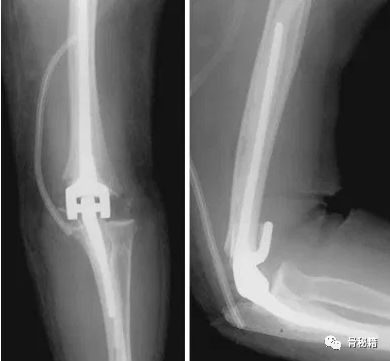

如果关节面粉碎,没法重建怎么办?

对于前方的关节面,可以不去重建不影响关节,肘关节的稳定主要是在内外侧滑车和肱骨小头这里要尽量重建,如果实在没有可以取髂骨进行重建,或者进行肘关节置换术。

最难的最难的。。。灾难级的!当开放骨折+大量骨缺损遇到了感染你会怎么办?

30岁年轻男性

病例的结局

一期行外固定架+抗生素骨水泥控制感染,这个是常规的。

下一步?

二期同种异体肘关节移植术!并且将三头肌支点与原肘进行了重建

术后18个月,出现了失败和关节的不稳,但宿主和自体骨较好的结合了。

又进行了第二次肘移植,最后终于愈合